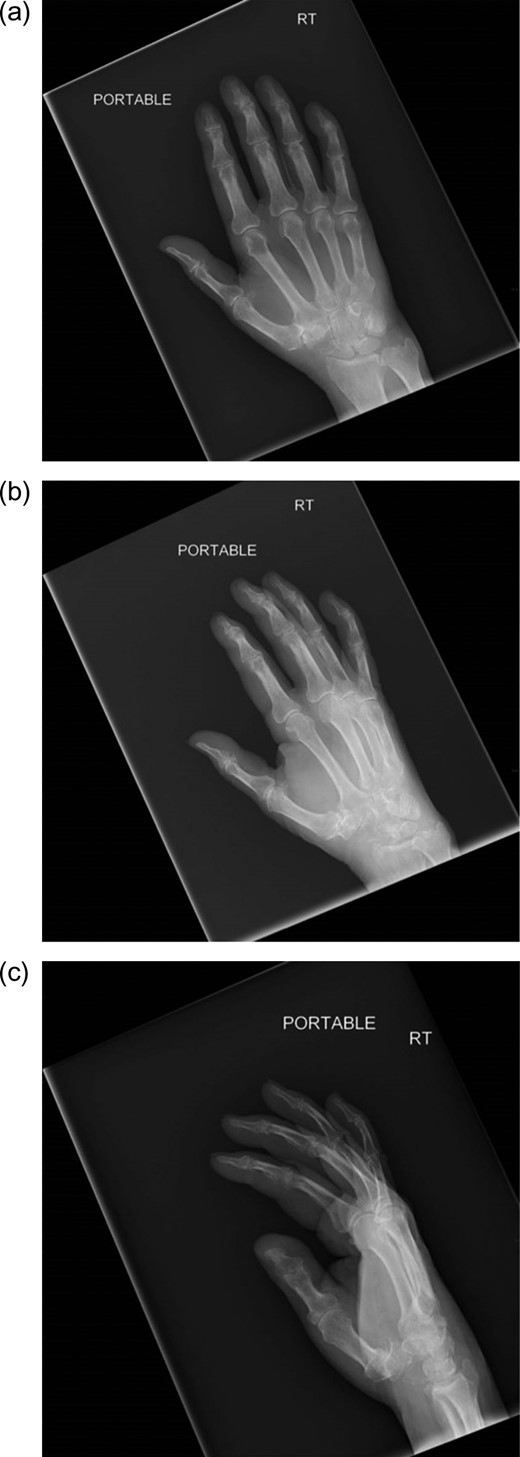

Radiographs of the right hand and wrist revealed a lytic lesion in the scaphoid with nearly complete destruction of the distal pole (Fig. 1a–c). The lateral radiograph also demonstrated some abnormal scalloping of the distal radius articular surface (Fig. 1c). Magnetic resonance imaging (MRI) showed destructive changes of the radial sided carpus (Fig. 2a and b), suggestive of neoplastic or infectious processes, but was inconclusive.

(a) AP image of the wrist showing a destructive lesion within the carpus. (b) Oblique image of the wrist showing a destructive lesion within the carpus. (c) Lateral view of the wrist showing a destructive lesion within the scaphoid. Note the near dissolution of the distal scaphoid and scalloping of the distal radius articular surface.